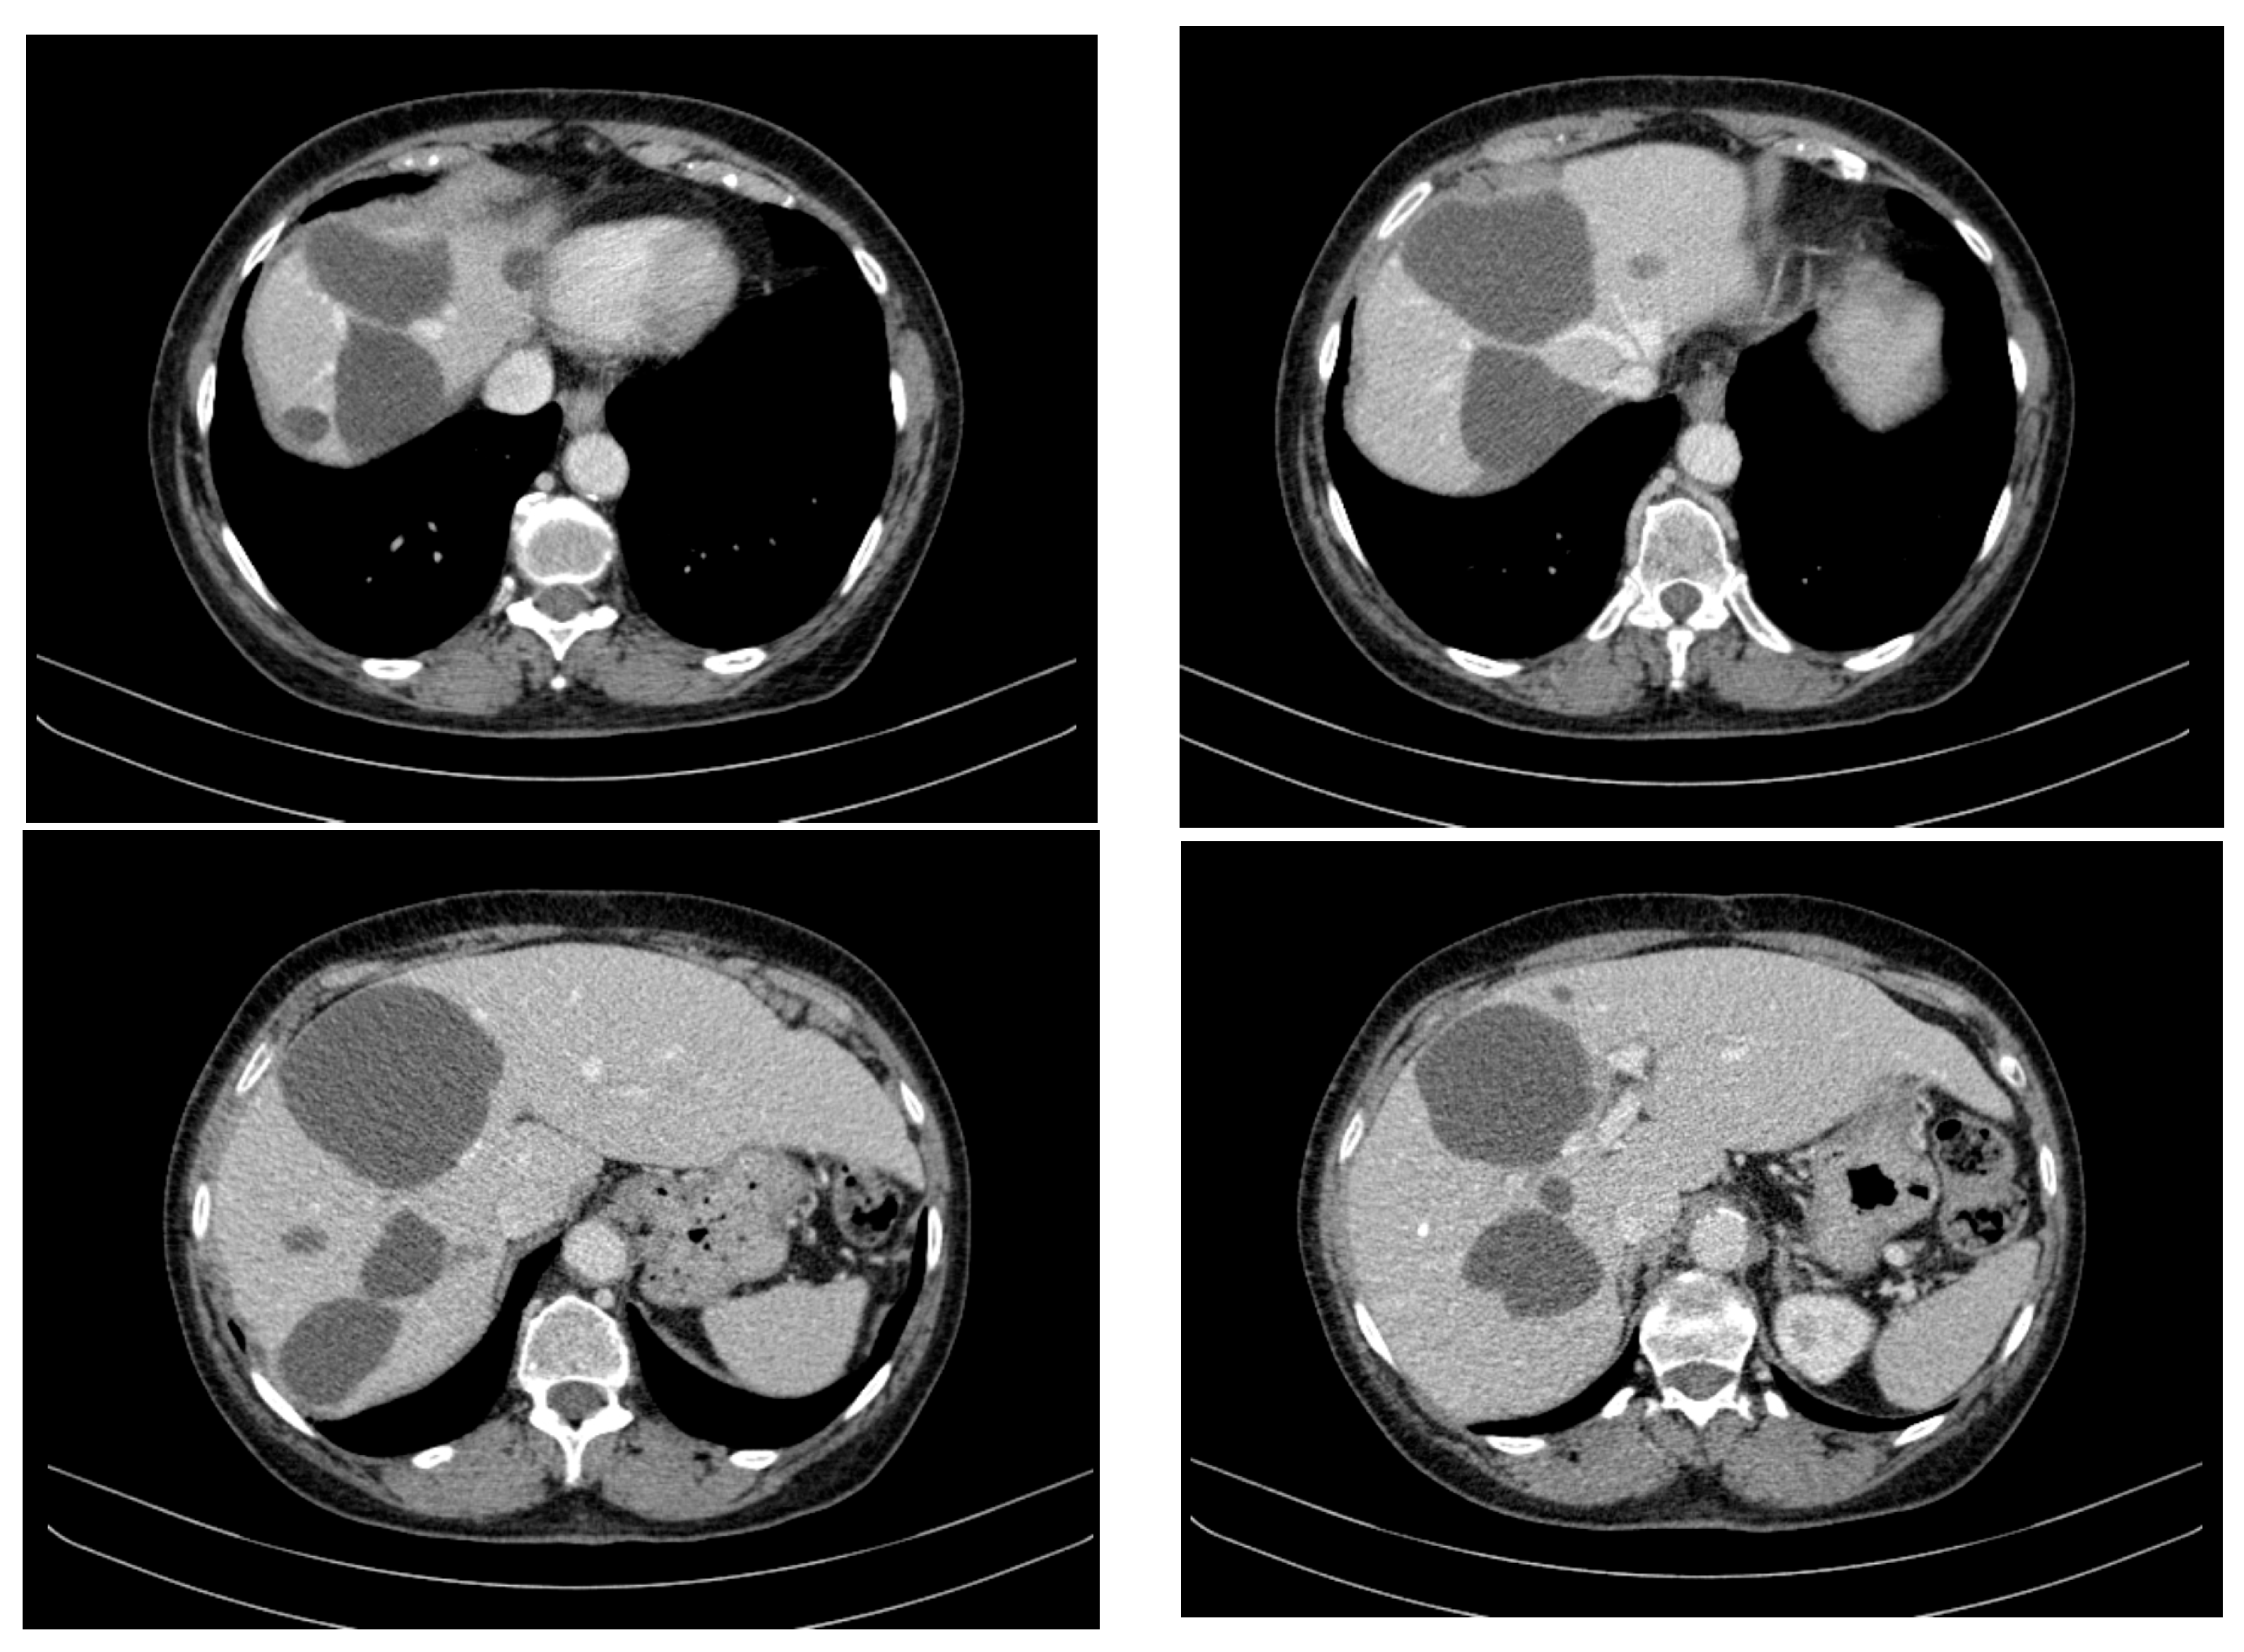

Over the course of 55 months of treatment with imatinib, the patient was monitored by imaging, exhibiting a stable disease course with no significant tumour progression and some evidence of partial regression of specific lesions. CT appearance at 12 months of treatment with imatinib is presented in Figure 3. The following key observations emerged from the serial CT evaluations:

Figure 3.

CT appearance at 12 months of treatment with imatinib at different abdominal levels.

- Hepatic tumour stability: Multiple large cystic hepatic lesions remained stable in size throughout the monitoring period, with no significant new secondary lesions developing. The largest hepatic cystic tumours persisted in segments IV, VI, and VIII, with maximum dimensions of ~8 cm, without major structural changes.

- Regression of extrahepatic lesions: Initial gastric and peritoneal lesions, including a cystic formation in the anterior gastric wall and ascitic fluid, regressed significantly by month 14 and did not reappear in later scans. The left inguinal hernia, although noted consistently, remained unchanged, without complications.

- Emergence of new findings without aggressive progression: A subcapsular nodule (3.5 × 2 cm) in Morrison’s space was identified during month 41, remaining stable without concerning enhancement patterns. A pseudo-nodular perfusion anomaly in segment VIII was noted but was attributed to pressure from the large cystic tumour rather than neoplastic progression. Mild gastric antral wall thickening developed later (by month 49), with a maximum thickness of 14 mm, but remained stable thereafter, with no associated adenopathy or signs of malignant transformation.

- Absence of significant distant metastases or new systemic involvement: Throughout the entire monitoring period, there were no newly detected secondary metastatic lesions in the thoracic, abdominal, or pelvic regions; no significant adenopathy was identified; and there was no recurrence of ascitic fluid beyond a mild amount in the early monitoring phases.